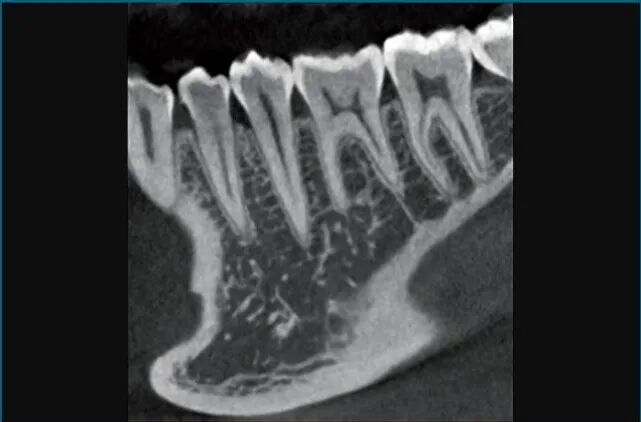

高清模式,HD75μm,可满足复杂的根管诊断

去除金属伪影,使图像更加清晰流畅,易于诊断